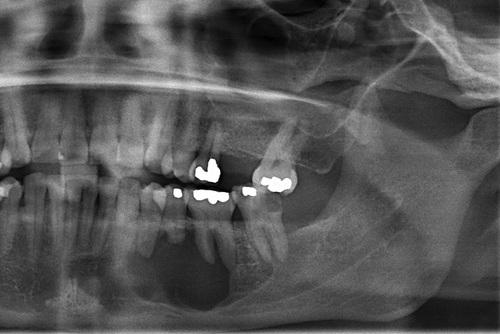

Radiographic Features

- well-defined radiolucent area

- large lesions may appear multilocular

- smooth and often corticated margins

- growth in an anteroposterior direction

- may involve an unerupted tooth (25% to 40%)

This large, multilocular cyst involves most of the ascending ramus and is growing in an anteroposterior direction.

odontogenic keratocyst (OKC)

This cyst involves the crown of an unerupted premolar, which appears similar to a dentigerous cyst.

Large cysts present in the right and left mandibular molar regions, together with a smaller cyst involving the right maxillary canine.

nevoid basal cell carcinoma syndrome